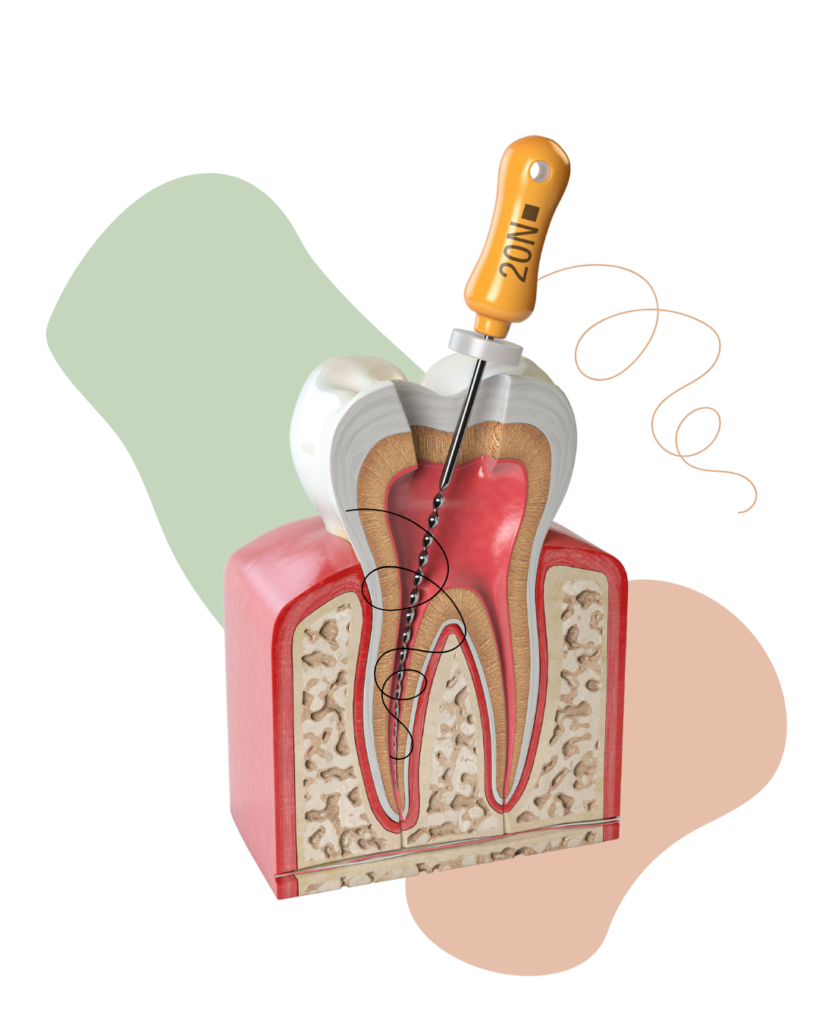

Jest to niezwykle istotna dziedzina stomatologii, dająca możliwość utrzymania własnych zębów i będąca podstawą prawidłowo wykonanej protetyki. Leczenie kanałowe w Studio Stomatologii i Implantologii jest bardzo ważną dla Naszej Praktyki procedurą, którą staramy się stale rozwijać i ulepszać, opierając się na nowoczesnych technologiach i materiałach. Podstawą do dobrego leczenia jest diagnostyka, do której wykorzystujemy system radiografii cyfrowej GENDEX oraz RYPEX firmy VDW służący do elektronicznego pomiaru długości korzenia. Kanał udrażniamy mikrosilnikiem SILVER VDW RECIPROC lub ultradźwiękami, do których używane są specjalne narzędzia obrotowe. Cała procedura odbywa się w powiększeniu mikroskopu. Odchodzimy od wypełniania kanału korzeniowego stosowanymi dotąd preparatami sterydowymi, zastępując je żywicami naturalnymi i syntetycznymi.

Wzmocnienie zęba włóknem szklanym to nowoczesne rozwiązanie, stanowiące alternatywę dla stosowanych do tej pory wkładów metalowych lanych i standardowych, wzmacniających ząb po leczeniu kanałowym. Stosujemy w Naszym Gabinecie zestaw wkładów z włókien szklanych firmy VDW (DT Light Post), który stanowi element całego systemu urządzeń i materiałów firmy VDW do leczenia kanałowego. Kanał opracowuje się mechanicznie przy użyciu specjalnych narzędzi. Następnie wypełniamy kanał korzeniowy specjalną żywicą. Do tak opracowanego i prawidłowo wypełnionego kanału cementujemy wkład, a następnie materiałem kompozytowym odbudowujemy zrąb korony i na tak przygotowane wzmocnienie wykonujemy koronę protetyczną lub wypełnienie.